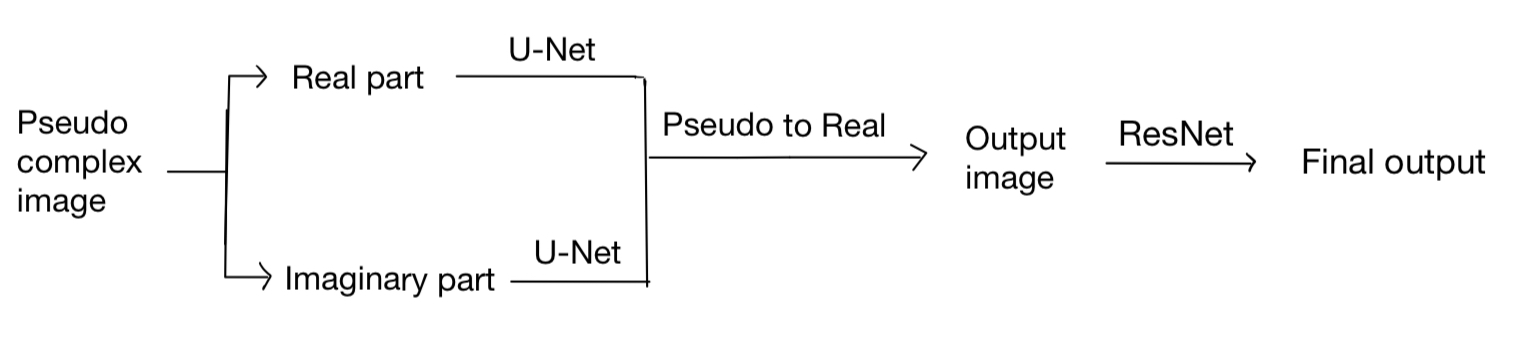

However, we find that the performance of our model is not good enough. Also, the training loss and eval loss are very close, which shows that our model may be more complex to improve the performance. Instead of only increasing the parameters of U-Net, we add another ResNet network after getting the Ouptut of U-Net. The final model is as follows: